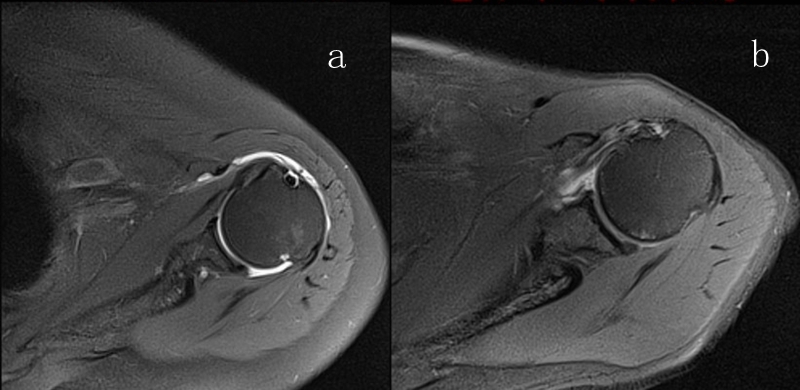

2、MRI检查

MRI目前是诊断肩袖疾病中最常用的检查,可以直观的观察肩袖肌腱。

图23 横断位a.正常肩胛下肌;b.肩胛下肌损伤